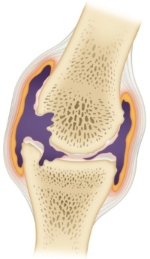

위의 그림은 류마티스가 순차적으로 진행되는 상태를 나타냅니다. 첫번째 초기단계는 관절낭 안쪽 활막에 염증이 생긴 상태입니다. 중간으로 접어들면서 관절이 붓고 물이 차며 연골이 손상됩니다. 결국 후기로 가면 섬유화가 일어나 뼈와 뼈가 붙어버리는 최악의 경우가 발생하게 됩니다.